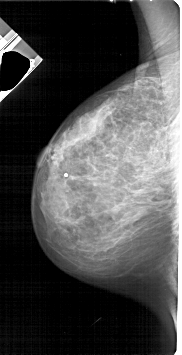

A_1713_1.LEFT_MLO

LEFT_MLO LINES 5311 PIXELS_PER_LINE 2716 BITS_PER_PIXEL 12 RESOLUTION 43.5 NON_OVERLAY